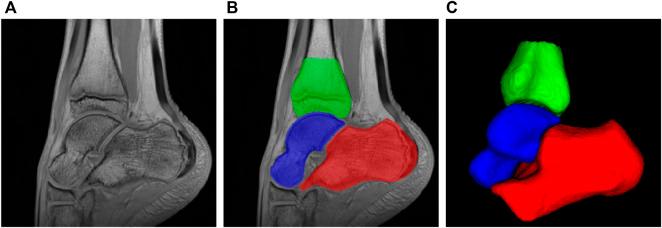

Cerebral palsy, a common physical disability in childhood, often causes abnormal patterns of movement and posture. To better understand the pathology and improve rehabilitation of patients, a comprehensive bone shape analysis approach is proposed in this article. First, a group analysis is performed on a clinical MRI dataset using two state-of-the-art shape analysis methods: ShapeWorks and a voxel-based method relying on Advanced Normalization Tools (ANTs) registration. Second, an analysis of three bones of the ankle is done to provide a complete view of the ankle joint. Third, a bone shape analysis is carried out at subject level to highlight variability patterns for personnalized understanding of deformities.

脑瘫是儿童期常见的身体残疾,常导致异常的运动和姿势模式。为了更好地理解其病理并改善患者的康复情况,本文提出了一种全面的骨骼形状分析方法。首先,使用两种先进的形状分析方法对临床MRI数据集进行组分析:ShapeWorks和基于体素的方法(该方法依赖于高级归一化工具(ANTs)配准)。其次,对踝关节的三块骨头进行分析,以全面了解踝关节。第三,在个体层面进行骨骼形状分析,以突出变异模式,从而个性化地理解畸形情况。